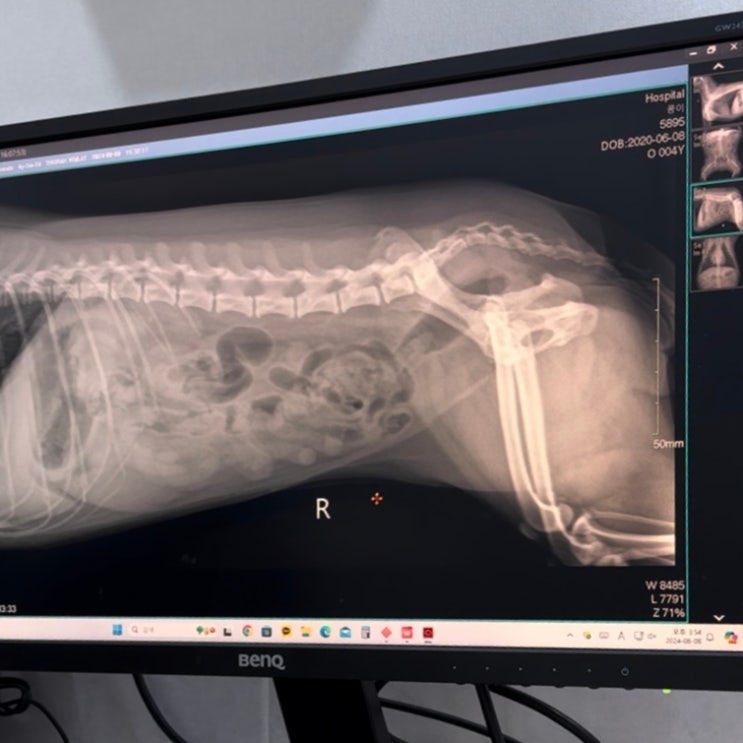

양천구 강아지 건강검진 동물병원 <서울탑동물병원> 슬개골 혈액검사

오늘도 라랄라~에요. :) 우리집 반려견 콩이는 올해 만 4살이 넘었어요. 지금까지 무탈하게 잘 지내고 있지...